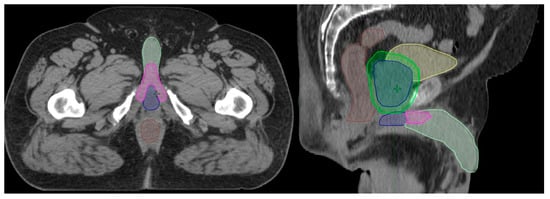

To ensure contour uniformity, the penile bulb, penile crus and penile shaft structures were retrospectively contoured or re-contoured by a single radiation oncologist with a primary practice in genitourinary malignancies, and doses were recalculated retrospectively. The penile bulb structure is defined and contoured as the portion of the bulbous spongiosum of the penis immediately inferior to the GU diaphragm, but without extension to the shaft or pendulous portion of the penis as seen on CT imaging [18]. To ensure the simplicity and reproducibility of contouring, the penile shaft (glans penis) structure was uniformly contoured as the entire penis excluding the penile bulb. This included the corpus cavernosum, corpus spongiosum, and penile shaft as visualized on CT imaging. An example of radiotherapy structure contouring is provided in Figure 1.

Figure 1. Example contours of the penile bulb (blue), penile crus (magenta), and penile shaft (light green) on axial and sagittal CT imaging. Other structures viewed in the image include the rectum (brown), bladder (yellow), prostate (blue), and PTV (green).